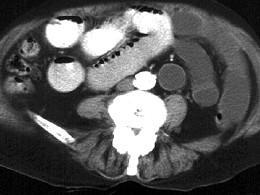

问题 女,60岁,反复左下腹隐痛约20年,伴包块外突2年余,站立或增加腹压后有一包块外凸,质地较软,平卧时消失且腹痛缓减,CT检查如图,最可能的诊断是 ( )

选项 A、腹壁转移瘤 B、盲肠炎 C、半月线疝 D、腹壁脂肪瘤 E、肠梗阻

答案 C